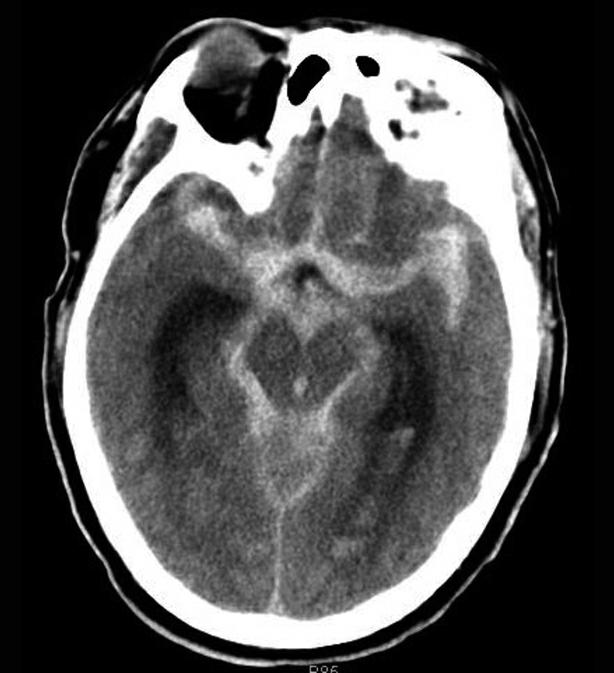

图1-2-94 蛛网膜下腔出血

双侧外侧裂池、环池、鞍上池、四叠体池、纵裂池及双侧大脑半球脑沟内示多发高密度影,CT值为72HU,双侧侧脑室后角可见高密度影